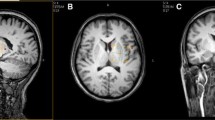

The spectral maps and the sums of the Cho, Cr and NAA signals of the quantified inner 6×6=36 CSI voxels (total volume 72 cm3) for one of the PKU patients measured at TEs 20, 40, 135 and 270 ms are shown in Fig. 1. The smaller portions of the spectrum shown at the shorter TEs (1.5–3.6 ppm rather than 0.5–4.3 ppm) reflect restrictions in the baseline ranges used for optimal baseline correction. The peak intensity scales for each spectrum are arbitrary, i.e., neither related to absolute concentrations nor suited for direct quantitative comparisons of measurements performed at different TEs.

a Spectral maps and b corresponding summarized spectrum in supraventricular VOI of PKU patient showing the resonances of Cho, Cr and NAA measured at TR=1,500 ms and TEs of 20 ms (upper left), 40 ms (upper right), 135 ms (lower left) and 270 ms (lower right). The frequency ranges vary per sequence with the applied baseline correction limits. Peak intensities, arbitrary units. Acquisition time: 6:31 min

It shows that with increasing TE the signals of Cho and especially Cr drop relatively to NAA. This reflects the order of the T 2 values that we observed in the PKU patients (Cr<Cho<NAA), similar to that in published control values (Table 1). At any TE the signal of Phe was close to the noise level, even in PKU patients (Fig. 2). The signal-to noise ratio in the 7.3-ppm Phe multiplet signal varied between 3 and 5, without a significant difference amongst the four TEs used. At TE=135 ms Phe was generally observed more clearly than at TE 270 ms or at the shorter TEs (20–40 ms). In analogy to the practice in previous MRS studies of PKU patients of measuring very large voxels in order to get sufficient signal per unit of measuring time, in our study the Phe signals from the individual voxels (2 cm3 each) of our CSI maps had to be summarized. Spectral map display of the array of individual Phe signals is therefore not meaningful.

The purpose of this study was optimization of the detection of Phe in the brain of PKU patients. Unlike in all previous studies, a multiple voxel method, CSI, was used here, and measurements were repeated at four different TEs. The spectral maps of Fig. 1a demonstrate that B 0 homogeneity of the magnetic field was excellent. This is evident from the resolution between the Cho and Cr peaks throughout the 8×8×2 cm3 VOI. Furthermore, the B 1 field was highly homogeneous as proven by the even distributions of peak heights throughout the VOI, indicating that the PRESS 90° pulses were effectively the same within the VOI. The good B 0 field allowed us to summarize the signals, a standard Vision “Numaris-3” option, of all CSI voxels without experiencing significant loss of spectral resolution (Fig. 1b). This validated our approach to summarize the spectra of all voxels prior to starting our Phe T 2 calculations (Fig. 2). In a single voxel of a CSI map the Phe signal was so weak that we had no alternative for summing the signals of all voxels. We conclude that for the detection of Phe multivoxel CSI offers no benefits compared with the large single voxel methods applied in previous studies [2–9].